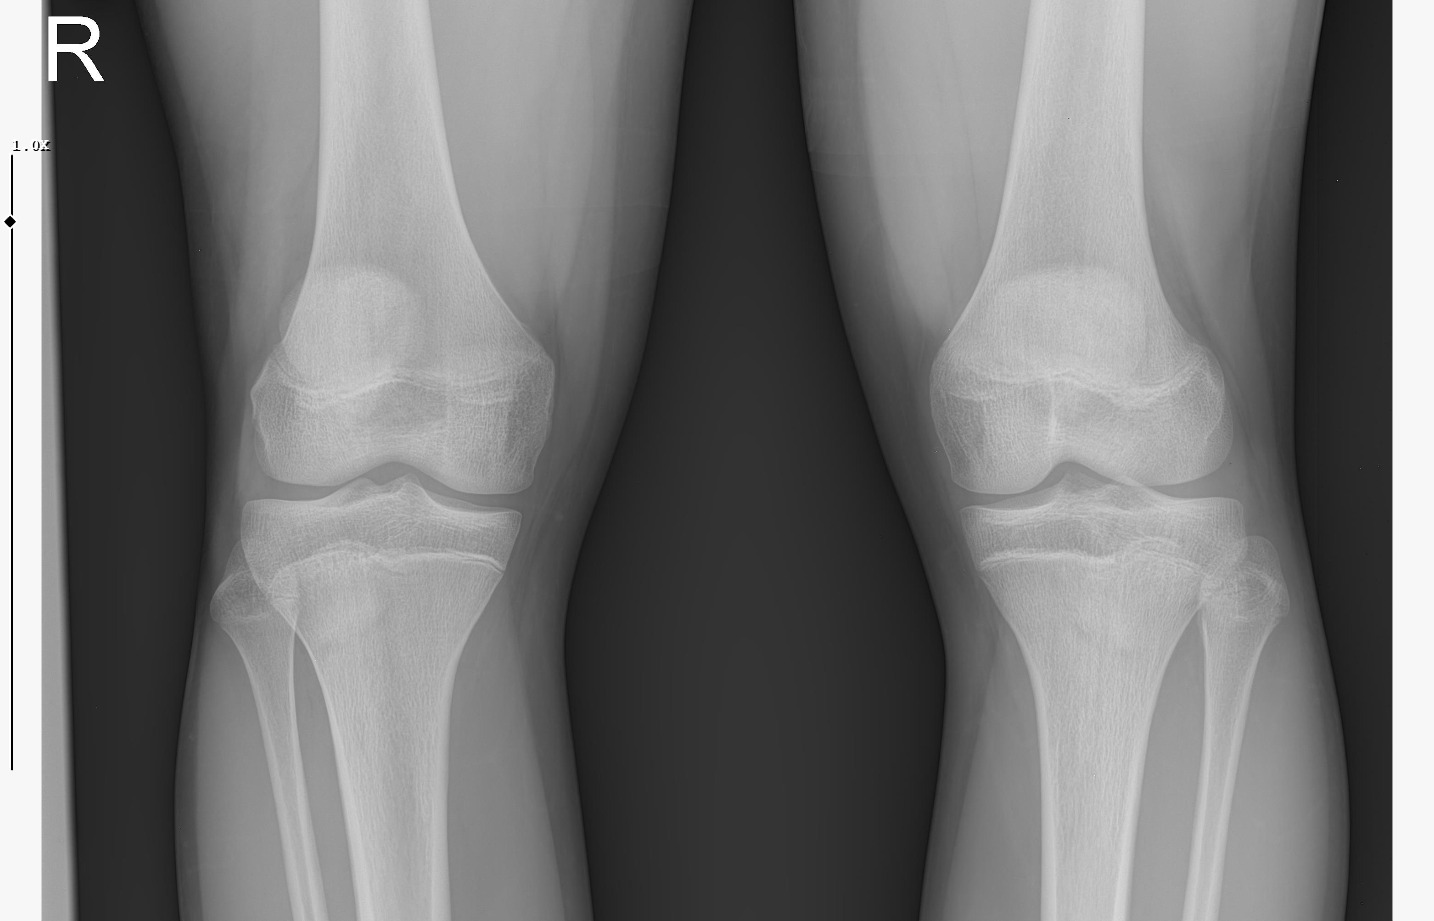

doktor bi sik bilmiyodur büyük ihtimalle plakları buraya at biz bakak

IMG 5959

röntgeni atar mısın?

• WhatsApp Image 2026-01-07 at 00.31.08 (4).jpeg

WhatsApp Image 2026-01-07 at 00.31.08 (4).jpeg

161.8 KB · Views: 0

• WhatsApp Image 2026-01-07 at 00.31.08 (3).jpeg

WhatsApp Image 2026-01-07 at 00.31.08 (3).jpeg

104.8 KB · Views: 0

• WhatsApp Image 2026-01-07 at 00.31.08 (1).jpeg

WhatsApp Image 2026-01-07 at 00.31.08 (1).jpeg

140.5 KB · Views: 0

• WhatsApp Image 2026-01-07 at 00.31.08.jpeg

WhatsApp Image 2026-01-07 at 00.31.08.jpeg

138.6 KB · Views: 0

kapanmaya baslamıs ama cok yakın degil

kemik yaşın 15 gibi 15'e çok yakın

anne baba boyun ve yaşını bilmiyorum sadece bu bilgilerle 171-175 arası diye tahmin ediyorum röntgen ile.

normalde anne babana göre 171-176 olman gerek zaten. kemik yaşın ve şuanki boyun ile yapılacak tahmin anne baban ile yapılabilecek tahminle nerdeyse birebir aynı yani büyük ihtimal o civarlar olursun bence